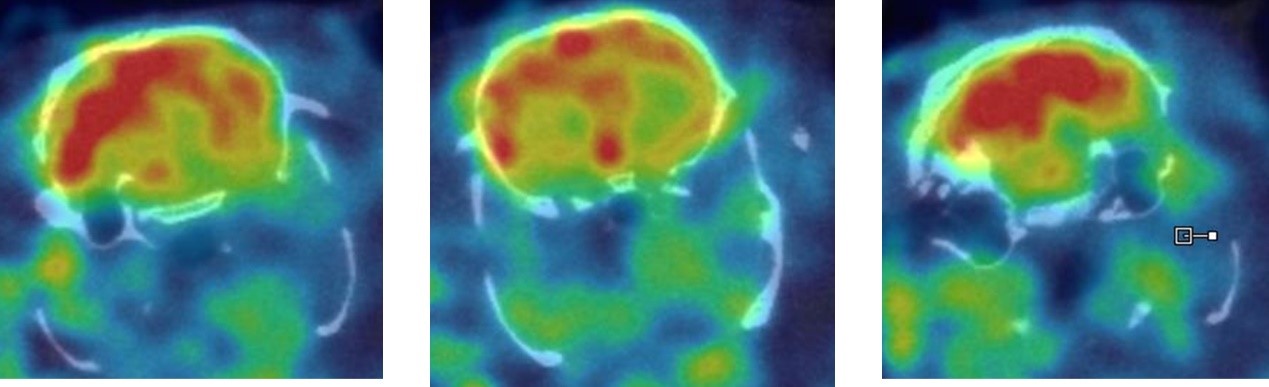

1、神經(jīng)系統(tǒng)SPECT成像

大鼠腦部SPECT成像:99mTc-HMPAO:腦血流灌注顯像劑,用于腦血管疾病,腦外傷,癲癇,癡呆癥,腦死亡的診斷;用于精神疾病的腦功能及正常腦生理功能活動(dòng)的研究。進(jìn)入腦組織的99mTc-HMPAO構(gòu)型改變而轉(zhuǎn)變成水溶性化合物,無法再次通過血腦屏障而滯留在細(xì)胞內(nèi),因此能在腦內(nèi)長(zhǎng)時(shí)間滯留。120 MBq,30 min uptake,30 min SPECT。